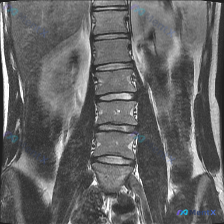

整理到一份很有意思的影像阅片病例: 有人看了一张腰椎MRI T2序列冠状位的图,第一反应是「脊柱侧弯(Scoliosis)」,但仔细读片后发现结论完全不一样。 先放核心影像表现: - 脊柱对线:腰椎序列基本连续,未见明显的侧弯或滑脱征象,椎体边缘清晰,无明显骨质破坏 - 椎间盘:下腰椎(L4/L5、...